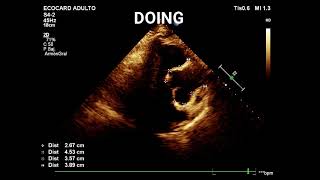

¿Cómo medir la raíz de aorta y aurícula izquierda?